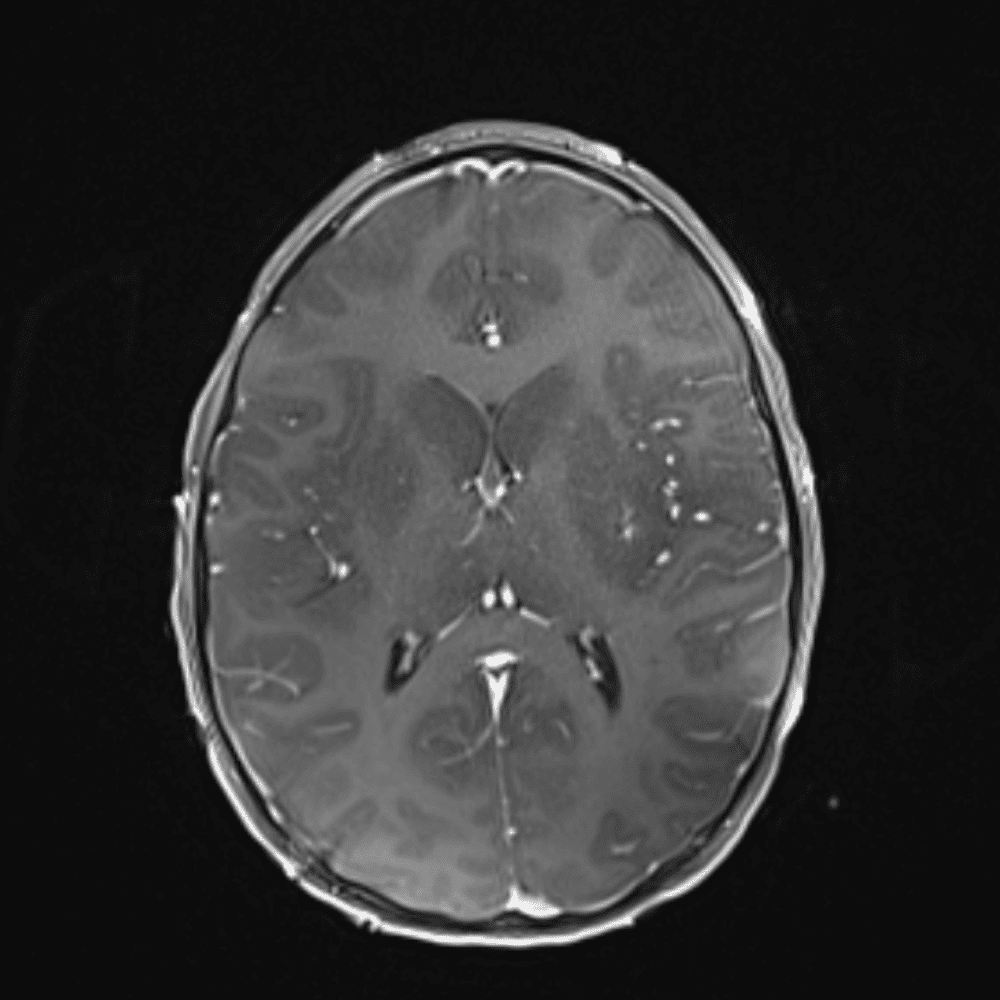

๋‹น์ง ์‹œ ํ”ํžˆ ๋ณผ ์ˆ˜ ์žˆ๋Š” ์‚ฌ๋ก€์˜ ์ „ํ˜•์ ์ธ ์˜ˆ๋ฅผ ํฌํ•จํ•ฉ๋‹ˆ๋‹ค.

39 ์‚ฌ๋ก€

์—ฐ์Šต

๋ฏธ๋ฌ˜ํ•˜๊ฑฐ๋‚˜ ์–ด๋ ค์šด ์‚ฌ๋ก€์™€ ์ผ๋ถ€ ์ •์ƒ ์‚ฌ๋ก€๋ฅผ ํฌํ•จํ•˜์—ฌ ๋‹น์ง์„ ์‹œ๋ฎฌ๋ ˆ์ด์…˜ํ•ฉ๋‹ˆ๋‹ค.

50 ์‚ฌ๋ก€